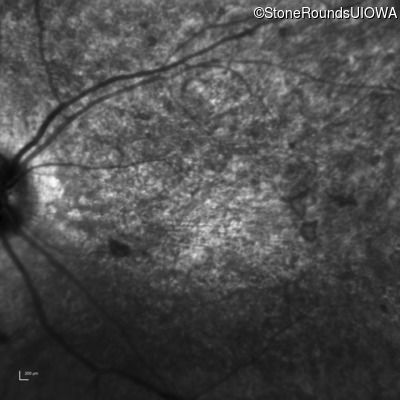

Infrared Fundus Photograph - Right - 20/400 sc

Exemplar